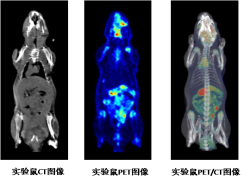

Super Nova系统扫描实验鼠PET、CT以及PET/CT融合图像

头部CT图像    头部PET图像  头部PET/CT图像

Super Nova系统扫描实验鼠头部PET、CT以及PET/CT融合图像